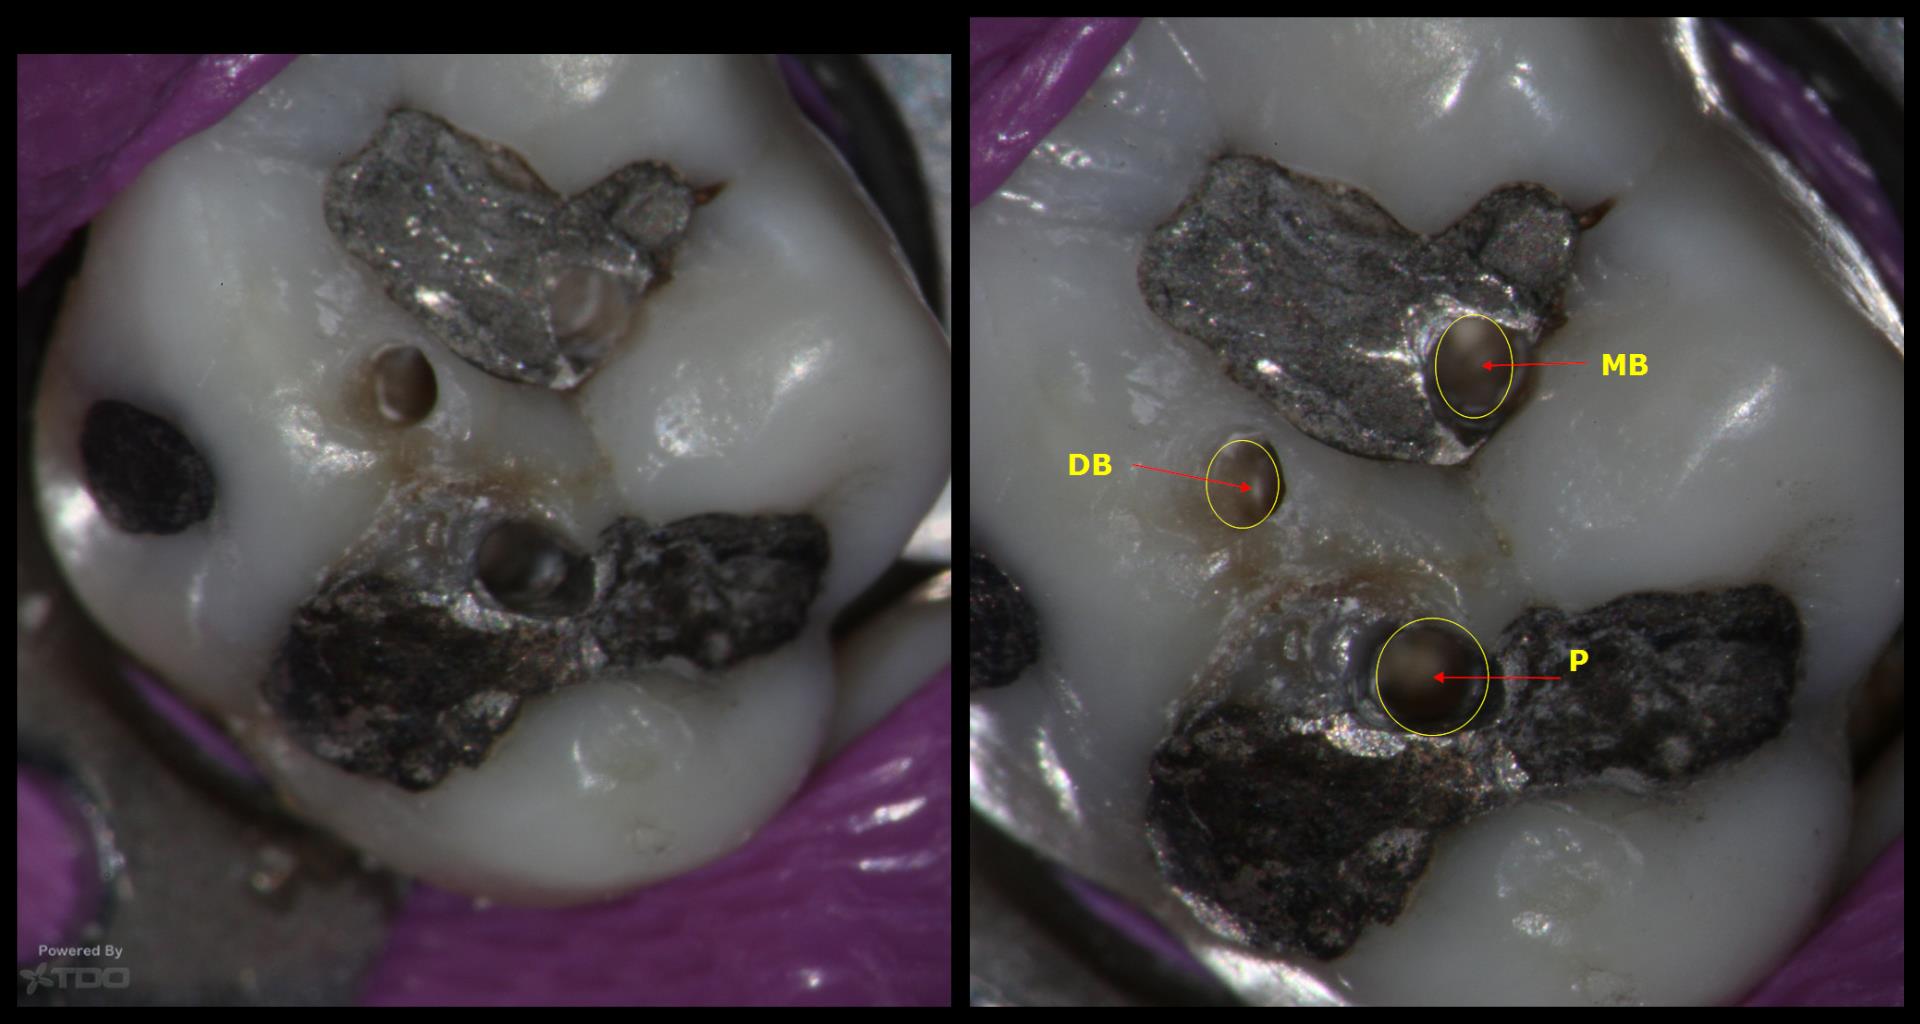

I have always wondered entry into the canal orifice requires precision but even more challenging is to be able to do it through 7-10 mm of dentin.

Any specific bur ? The angles of entry ?

Any slim ultrasonic to smoothen the entry point into dentin and the canal orifice ?

What kind of motions in this access referring to ergonomics ?